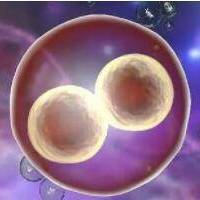

2. 冷冻技术的使用

玻璃化冷冻技术使用卵子/胚胎冻结生存率达96%以上,为跨境治疗提供时间弹性。建议尽早完毕取卵/男性生殖细胞体冷冻,避免频繁往复。